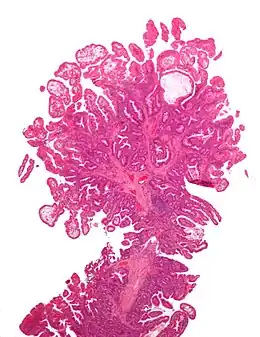

| Adénome tubulaire (villositaire, tubulovilleux) | Glandes tubulaires avec des noyaux allongés (au moins à faible teneur atypie) | Oui | ![]() |

||